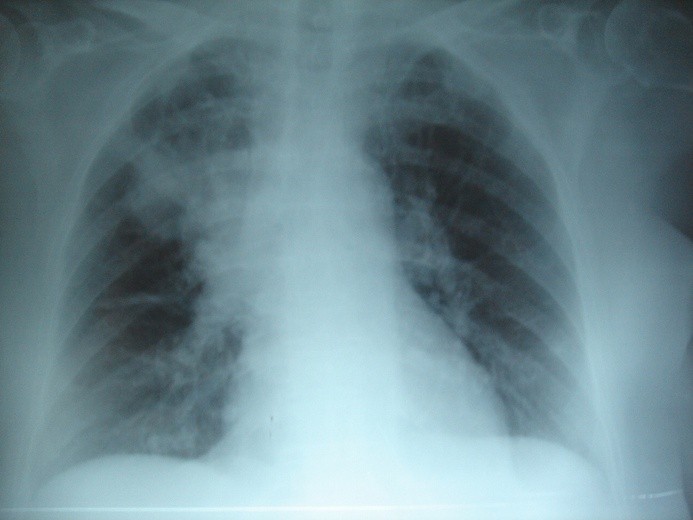

U chorych na mukowiscydozę obserwuje się m.in. przewlekły, suchy kaszel, duszności, częste, nawracające infekcje oskrzeli i płuc oraz przewlekłe zapalenie zatok przynosowych i powstawanie polipów.